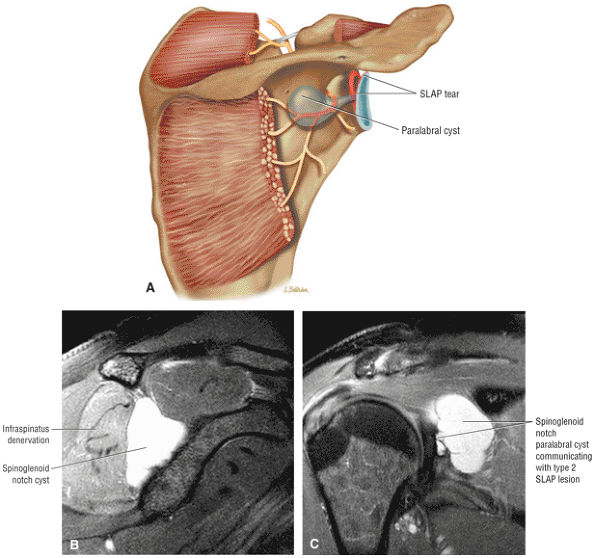

The scapula consists of the scapular body, the scapular spine, the scapular neck, the acromion, the glenoid fossa, and the coracoid process.44 The subscapular fossa represents the costal concave surface of the scapula. The dorsal convex surface of the scapula is separated into supraspinous and infraspinous fossae divided by the spine of the scapula. The suprascapular nerve is located in the supraspinous or spinoglenoid notch, at the superior border of the supraspinous fossa. Compression of the suprascapular nerve by a ganglion or entrapment, secondary to thickening of the suprascapular ligament, occurs in this location.